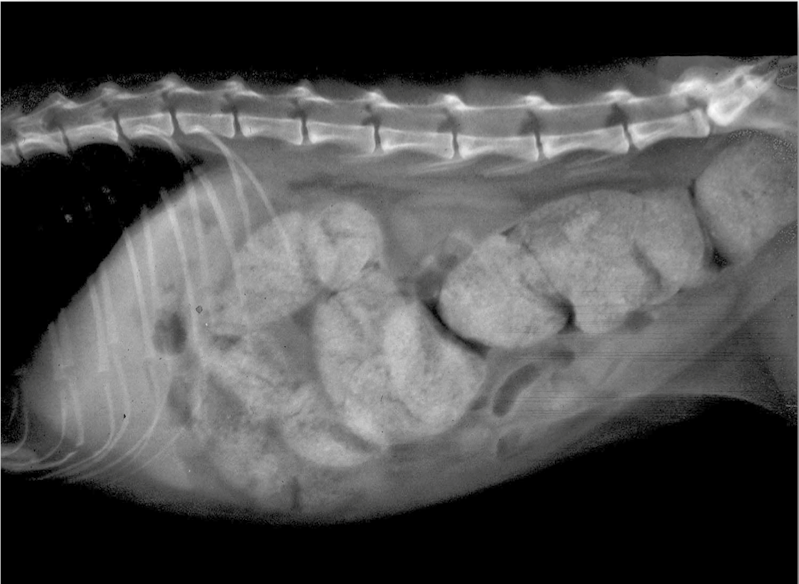

What is this showing?

obstipation